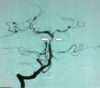

123

What artery are the arrows in this image pointing to? a) Anterior communicating b) Posterior communicating c) Middle cerebral d) basilar e) Vertebral

124